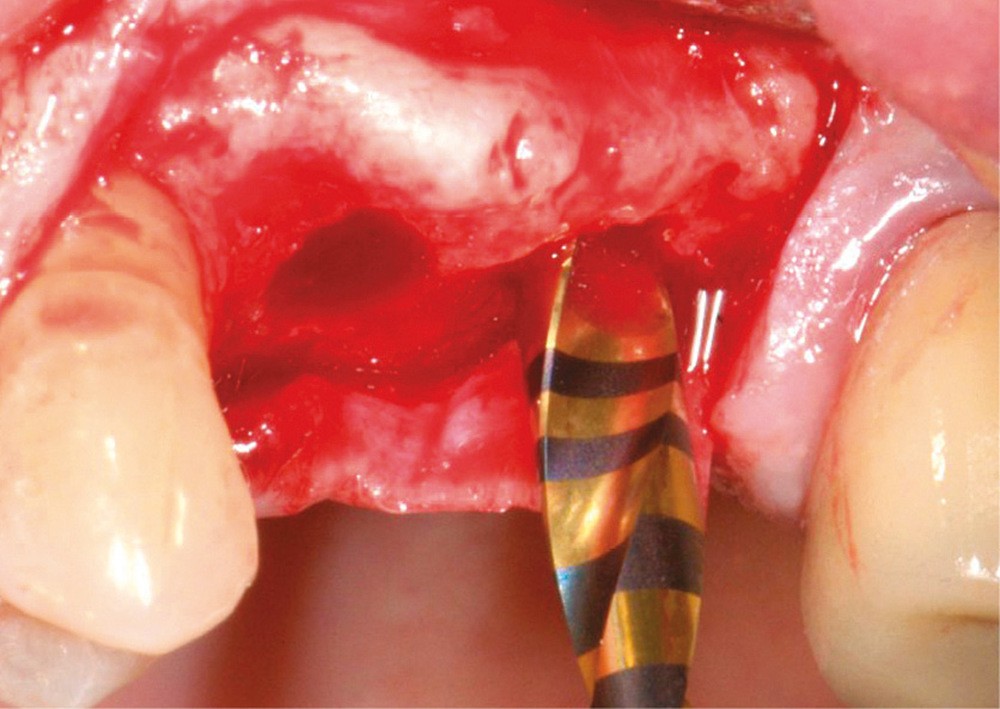

Notre objectif est ici de proposer une modification de la technique initiale conduisant à un plus grand confort opératoire pour le patient tout en sécurisant ce comblement. Ce protocole opératoire simplifié pour un soulevé de sinus crestal prévisible, est illustré à travers un cas clinique avec son protocole (fig. 1 à 10).

L’abord crestal, imaginé par Tatum en 1986 (père également de la voie latérale, désignée aussi par « la fenêtre de Tatum »), a été repris par Summers qui décrit la technique d’ostéotomie crestale en 1994. Sa technique, faisant appel à une série d’ostéotomes, a subi plusieurs modifications dans le temps. Citons entre autres « the modified osteotomes technique », décrite en 1996 par Davarpanah et al, ainsi que « the bone added osteotomes sinus floor elevation (BAOSFE) technique », décrite par Rosen et al en 1999. Dans…